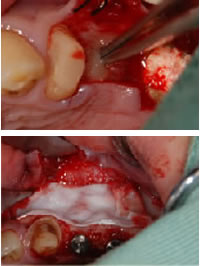

4.再生治療

再生治療

できたフィブリンゲルは、再生治療に使用します。骨を作製したい部分に埋入(上の写真)したり、平たくつぶしてメンブレンとして使用(下の写真)したりします。

メンブレンとは歯槽骨を造成するための膜のことです。